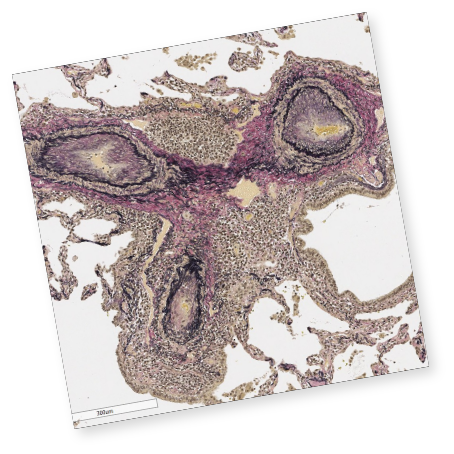

クイズで学ぶILDとILD-PH診断のポイント

実症例をもとに、画像や検査データから

間質性肺疾患および間質性肺疾患に伴う肺高血圧症の診断ポイントをクイズ形式で確認。

実践に即した診断力を養います。